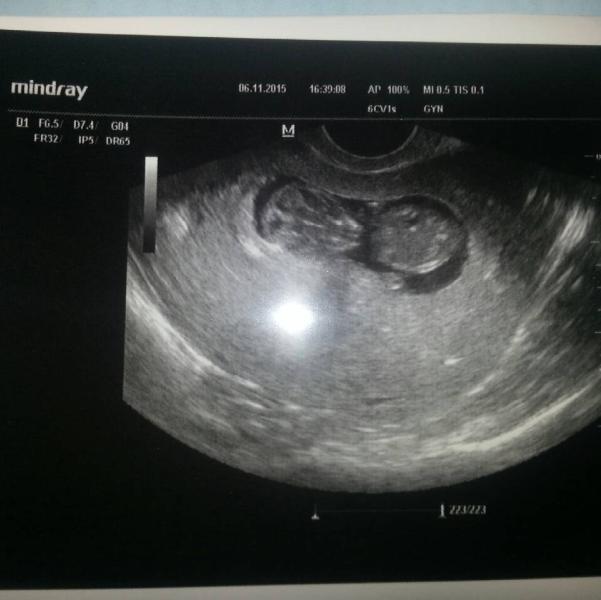

Мое первое узи! Сказали все хорошо, поставили 9-10 недель, видно маленькие ручки, я так СЧАСТЛИВА!